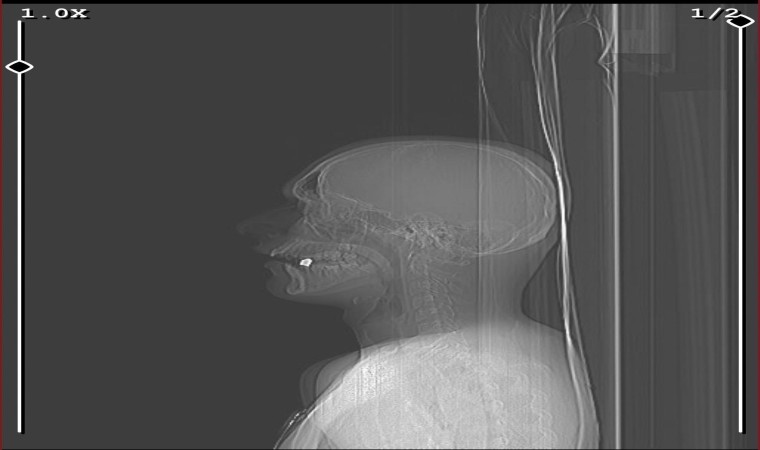

Pendik’te arkadaşlarıyla dondurma almaya giden 17 yaşındaki genç, cadde üzerinde seyir halinde oldukları aracın içerisinden rastgele açılan maganda kurşununun hedefi oldu. Kurşun 17 yaşındaki gencin boynundan girip ağzında kaldı. Ateş açan şahıslar ise olay yerinden kaçarak uzaklaştı.

Olay, geçtiğimiz Pazartesi günü gece 02.00 sıralarında Pendik’te Velibaba Mahallesi’nde meydana geldi. Edinilen bilgiye göre, 17 yaşındaki Aykan Yazar arkadaşıyla birlikte dondurma yemeye gitti. Yazar evine döndüğü sırada, aracıyla seyir halindeyken havaya ateş açarak ilerleyen kimliği belirsiz bir magandanın kurşununun hedefi oldu. Kurşun Yazar’ın ensesinden girerek ağzında kaldı. Şans eseri hayatta kalan Aykan Yazar ihbar üzerine olay yerine gelen ambulans ile ekipleri ile hastaneye kaldırıldı. Polis ekipleri ise kimliği belirsiz magandayı yakalamak için çalışma başlattı.